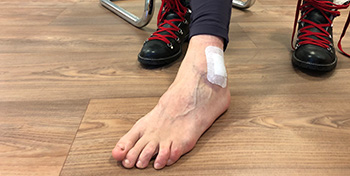

- Ganglion located on the side of the ankle, causing much discomfort during hikes or when wearing ski boots. US aspiration had been unable to fully drain it.

- Day 0 – Just after surgery ready to go home. Soft bandage over the ankle to allow wearing normal shoes